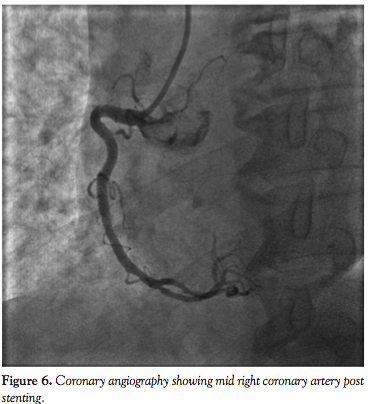

For the overall study group, there were no peri- or postprocedural MACEs. Mean fluoroscopic time was 25.3 ± 17.2 minutes and mean contrast volume was 203.1 ± 80.1 mL. Figures 1 through 8 illustrate our experiences with Integrity coronary stents in some of the “classical” tortuous coronary vessels.

One striking feature we observed about the Integrity coronary stent was that it conformed very well to the vessel wall (Figures 1-8). This is important, since it means the stent has sufficient radial strength to resist the elastic recoil of the media and can mold its shape along the contour of a curved segment with minimal vessel straightening and provide a large desired lumen. When the DES is implanted, excellent apposition of the struts on the vessel wall will ensure uniform delivery of the cytostatic drug to prevent neointimal hyperplasia. An in vitro conformability test15 has shown the Integrity DES to have better strut apposition and lower vessel wall stress when compared to other market-leading DESs. This has